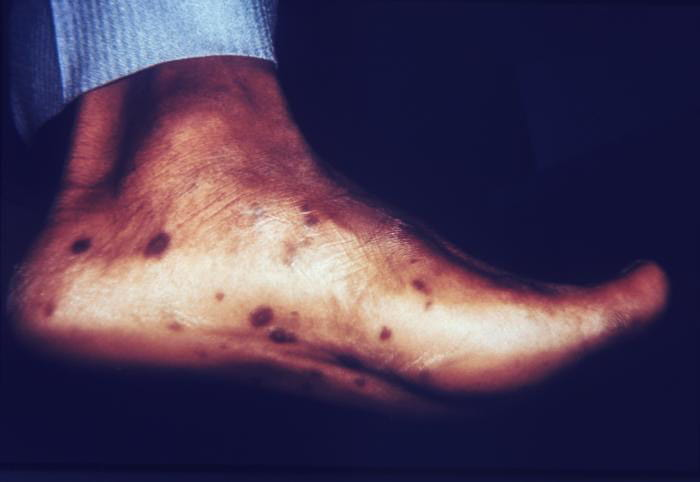

梅毒疹:皮损内含有大量TP,传染性强,不经治疗一般持续数周可自行消退。皮损通常缺乏特异性,可表现为红斑、丘疹、斑丘疹、斑块、结节、脓疱或溃疡等,常以一种类型皮损为主,大多数泛发,不痒或轻微瘙痒。斑疹性梅毒疹表现为淡红色或黄红色斑疹,直径0.2~1cm,类似于病毒疹、玫瑰糠疹、麻疹猩红热样药疹或股癣等。丘疹性梅毒疹表现红色丘疹、斑丘疹,表面可脱屑或结痂,类似于皮炎、湿疹、扁平苔藓、银屑病等。表现为红色斑块或结节的梅毒疹常误诊为皮肤淋巴瘤。脓疱性梅毒疹多见于体质衰弱者,表现为潮红基底上的脓疱,可伴发溃疡或瘢痕形成。掌跖部位梅毒疹表现为绿豆至黄豆大小、铜红色、浸润性斑疹或斑丘疹,常有领圈样脱屑,互不融合,具有一定特征性。

银屑病的掌跖部皮损常为角化性斑片,有时覆少许鳞屑或出现被裂。该皮损与二期梅毒的掌跖损害完全不同。